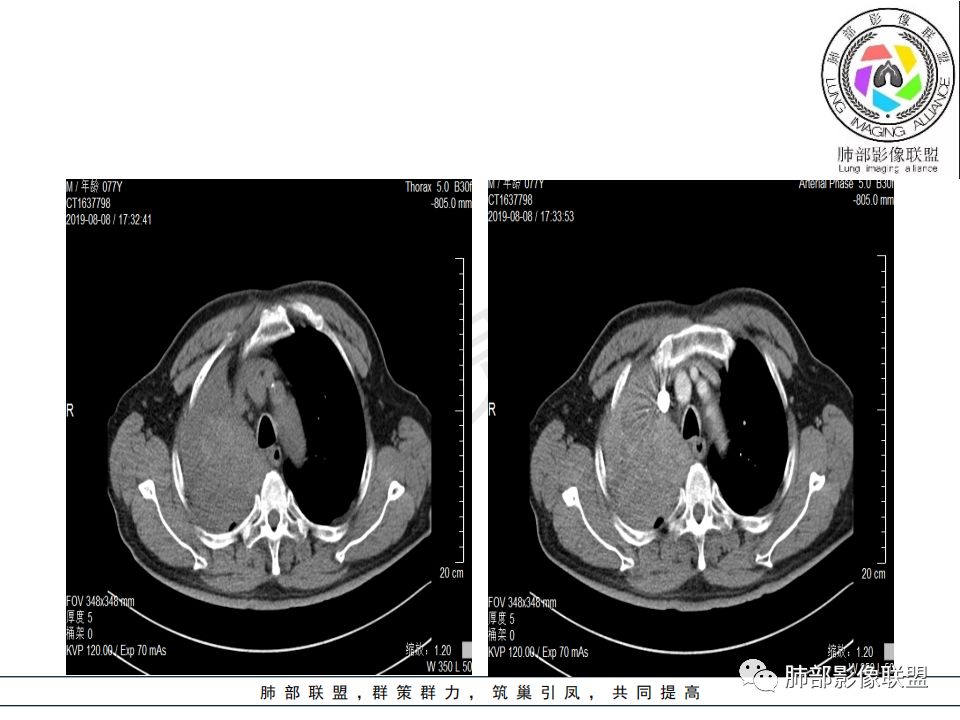

右肺主支气管有软组织肿块,向腔内外生长,右肺上叶肺不张,边缘光滑,增强扫描不均匀强化。考虑恶性肿瘤,鳞癌可能。

晨读,右肺主支气管有阻塞,腔内.腔外都见软组织影,右肺上叶不张,肿块内部密度不均匀,是不是有坏死影,老年男性,考虑恶性~鳞癌

晨读:患者老年男性,以咳嗽一月就诊,少量白痰,胸CT:纵隔右移,右肺体积缩小,气管下段管壁可见结节样改变,气管软骨变形,气管下段及右主支气管可见新生物向管壁浸润,并向管腔外生长,右上肺肺不张,但不张边缘可见病灶呈膨胀性生长,可见分叶,增强后强化明显。考虑:肺部恶性病变(鳞癌?)

右肺上叶肿块,边缘光滑,略膨隆,近段支气管堵塞,平扫密度均匀,增强后不均匀强化,其内可见不规则血管和坏死,纵隔淋巴结肿大,老年男性,无感染性病史,综合考虑恶性肿瘤(鳞癌,腺癌),鉴别:OP(一般下叶多见)